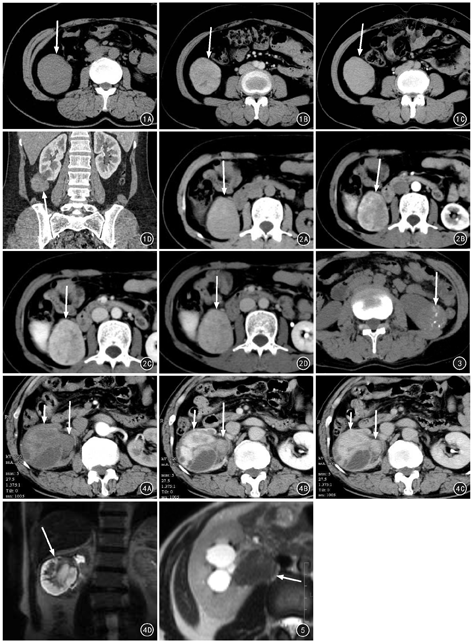

CT平扫肿瘤边界均显示清晰,5个病灶呈高密度,2个呈等密度;6个病灶密度均匀,1个密度不均,肿块内见明显的坏死、囊变。见图1、图2。2个病灶内见钙化灶,呈多发斑点状(图3)。动态增强扫描肿瘤均呈明显强化,CT值较平扫增加51~99 HU。5个病灶呈渐进性延迟强化的特点:皮质期轻度强化,随着时间的延迟强化程度明显增加,以肾盂期强化最为显著(图1B、图1C、图1D)。2个病灶在肾盂期强化程度较实质期分别下降20 HU和18 HU,但强化范围增大且趋向均匀(图2B、图2C、图2D)。6个病灶呈基本均匀强化,肿块内未见明显坏死囊变。1个病灶肿瘤坏死囊变明显,实性成分呈延迟明显强化的特点,坏死囊变区无明显强化,肿瘤包膜轻度强化(图4A、图4B、图4C)。1例伴肾盂积水扩张,6例均未见肾静脉及下腔静脉瘤栓形成。肾门或腹膜后均未见明显肿大淋巴结影。

MRI检查2例共3个病灶,1个病灶信号不均,肿瘤坏死囊变明显,T1WI、T2WI均呈高低混杂信号,T2WI上病灶周围可见完整的低信号肿瘤包膜(图4D);2个病灶信号均匀,其中1个呈T1WI低、抑脂T2WI略高信号,1个呈T1WI等、T2WI明显低信号(图5)。1例单发者行MRI动态增强扫描病灶强化方式与CT相似,表现出延迟强化特点,且强化均匀。

6例共发现7个平滑肌瘤病灶,肿瘤最大径2.5~7 cm,平均5.3 cm;其中5个位于右肾,2个位于左肾;5个位于肾脏边缘,1个位于肾实质内,1个位于肾盂。肿瘤呈圆形和椭圆形各3个,呈分叶状1个。CT平扫5个病灶呈高密度,2个呈等密度;1个病灶密度不均,肿块内见坏死、囊变,其它6个密度均匀。CT增强扫描7个病灶均表现出渐进性延迟强化的特点,其中6个呈均匀强化,1个强化不均。MRI平扫2例共检出3个病灶:2个信号均匀,其中1个呈T1WI低信号、T2WI略高信号,1个呈T1WI等信号、T2WI明显低信号;1个信号不均,T1WI、T2WI均呈高低混杂信号,T2WI上病灶周围可见低信号肿瘤包膜;2个瘤体内见斑点状钙化。MRI增强检查1个病灶呈均匀延迟强化。